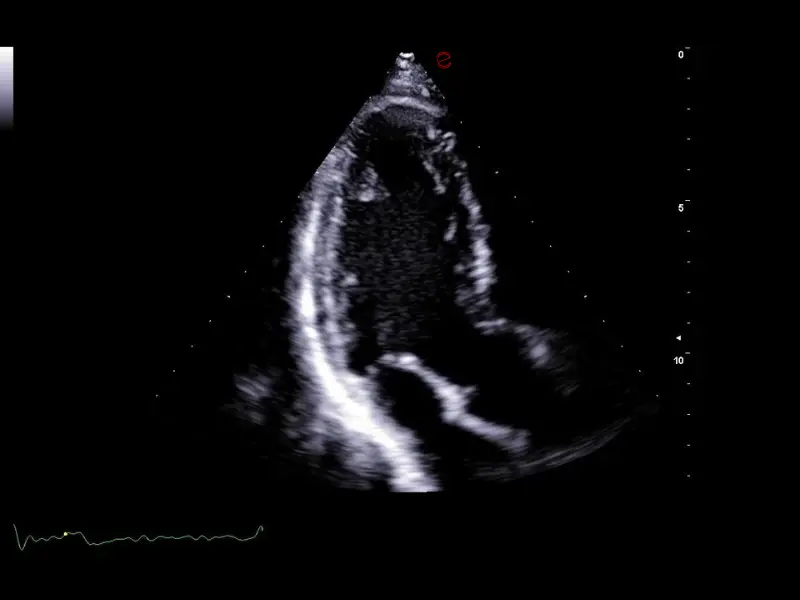

Q7 - CV Cardio B-mode

Q7 - CV Cardio B-mode

Q7 - CV Cardio B Mode 2

Q7 - CV Cardio B Mode 2